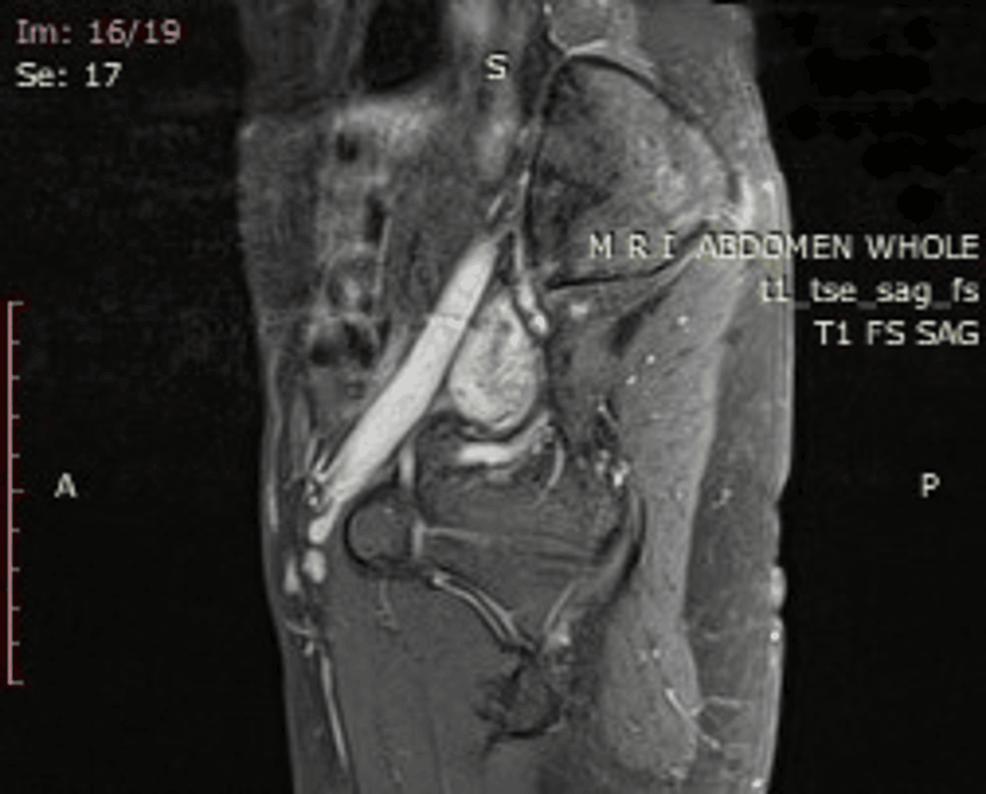

Deep Venous Thrombosis Do Blood Clots Show Up On Mri One study used direct thrombus. An mri can provide images of your veins that may show if a blood clot has formed. For example, in people with atrial fibrillation, clots are usually found in the left atrium of the heart. Yes, mri can detect blood clots. Magnetic resonance imaging (mri) may be used to diagnose deep vein thrombosis (dvt) in. Do Blood Clots Show Up On Mri.